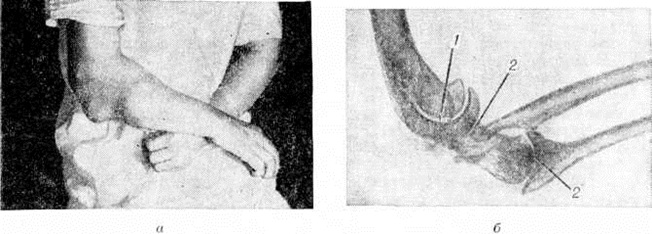

Наряду с остеолитическими процессами возникают и выраженные гиперостотические изменения в виде чрезмерных, причудливой формы напластований костной ткани, окостенений мягких околосуставных тканей. Разрушение и созидание костной ткани происходит беспорядочно, хаотично. Одновременно появляются изменения и в связочном аппарате — расслабляются суставная капсула, связки, что способствует чрезмерной подвижности в суставе, разболтанности, резко выраженному смещению костей сустава — патологический Вывиху (смотри полный свод знаний). Различают две формы остеоартропатий — остеолитическую и гиперостотическую, которые протекают соответственно с преимущественно деструктивными, литическими, изменениями или с гиперостозом (смотри полный свод знаний) — значительным костеобразованием, с причудливым утолщением кости и уплотнением её структуры (рисунок 4).

При Сирингомиелия чаще всего поражаются локтевые суставы, несколько реже — плечевые. Лучезапястные и межфаланговые суставы поражаются редко. В пальцах кисти встречаются изменения главным образом в виде остеолиза ногтевых фаланг, а также разрушения межфаланговых суставов.

Наиболее выраженные изменения наблюдаются в костях локтевых суставов. В плечевых суставах деструктивные костные изменения менее выражены, чаще они проявляются частичной деструкцией головки плечевой кости и суставной впадины лопатки (рисунок 5). Обычно, несмотря на большие деструктивные костные изменения, остеопороз не отмечается.

Кроме остеоартропатий, при Сирингомиелия наблюдаются и остеопатии — трофические внесуставные изменения в диафизах длинных трубчатых костей, главным образом в костях предплечья, в виде локальных гиперостоза и рассасывания, приводящих к патологический переломам и образованию ложных суставов (рисунок 6). Так, иногда в локтевой кости наблюдаются зоны перестройки и остеолиза (рисунок 7), приводящие к нарушению целости кости и спонтанному перелому. Описаны своеобразные изменения скелета в виде увеличения костей кисти — так называемой хейромегалии.